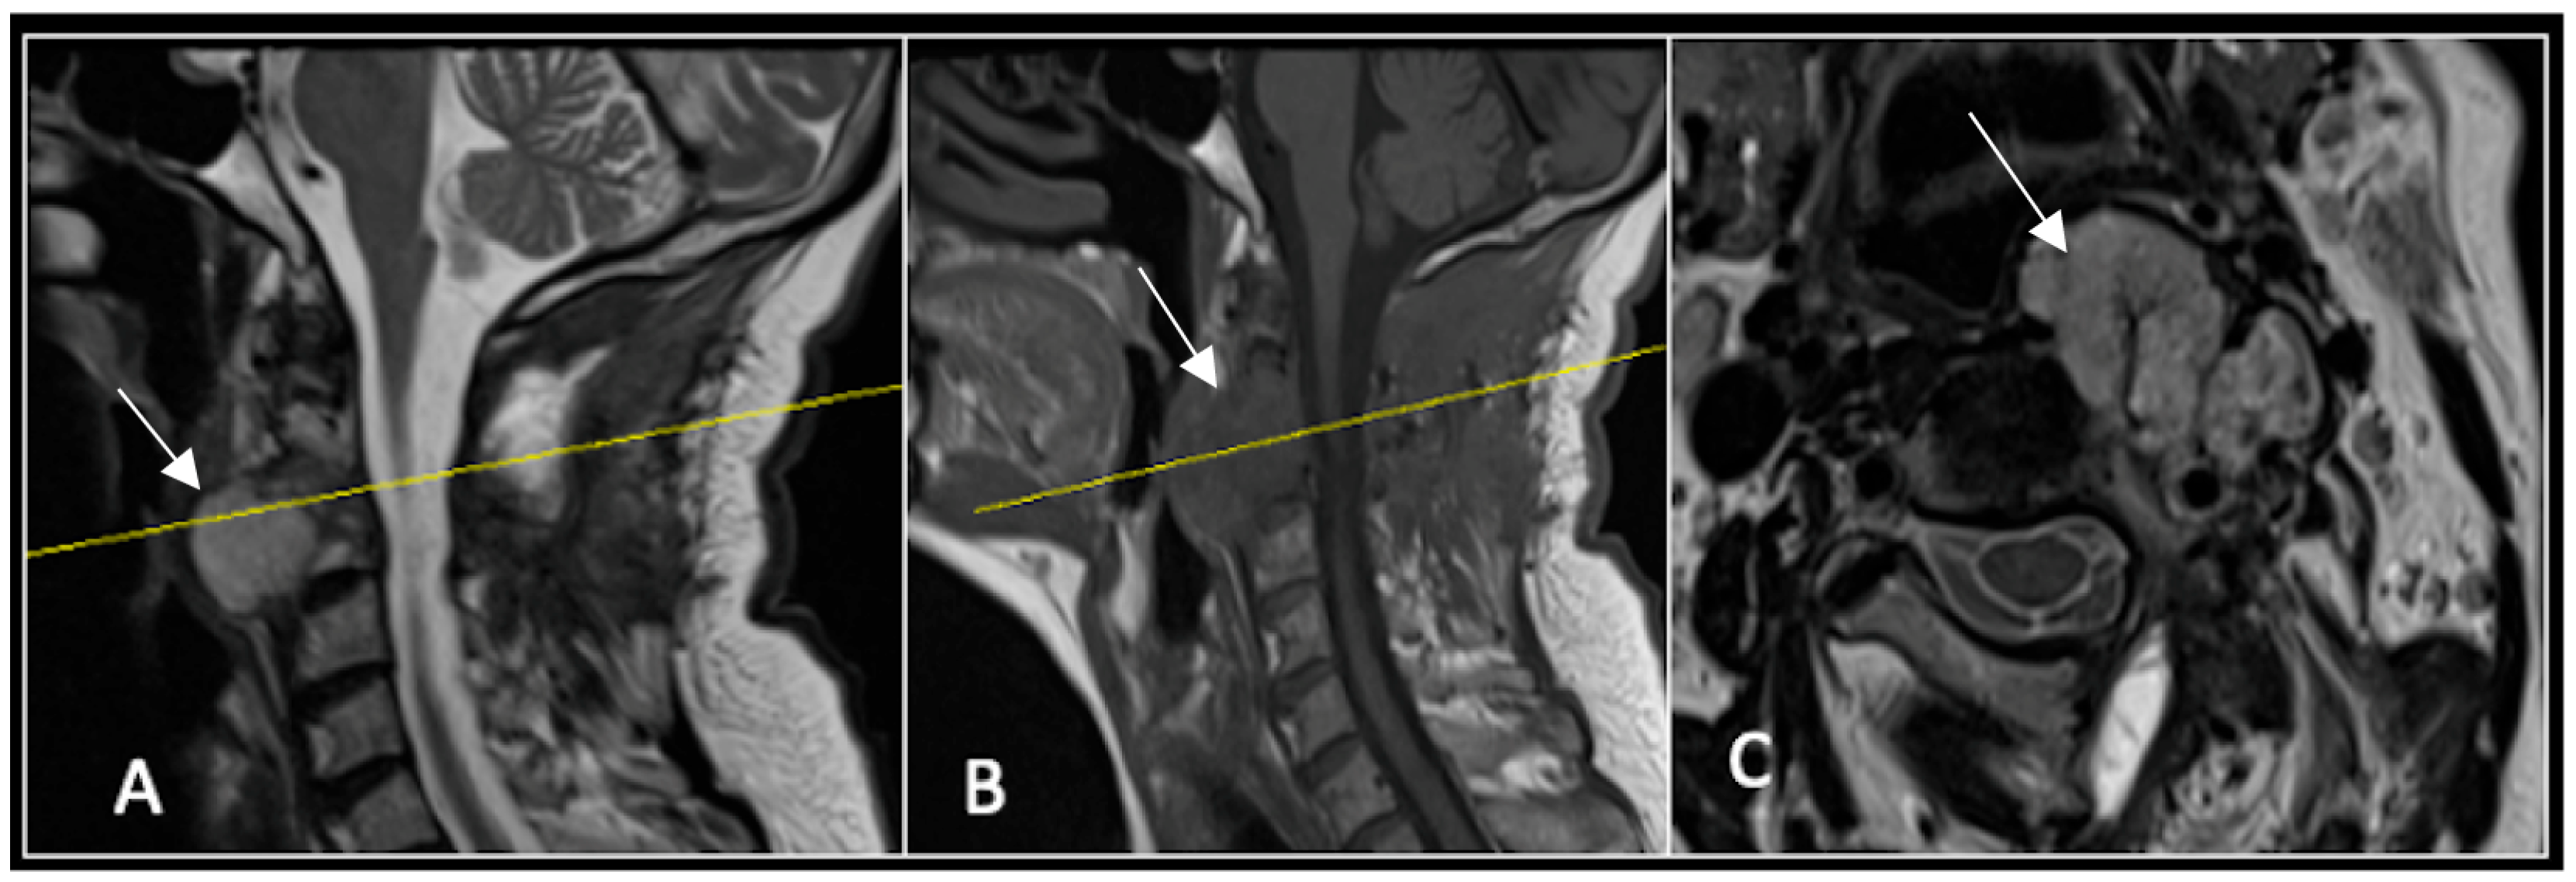

This 68-year-old male was referred to our institution with a 4 cm cervical mass localised to C2/3 following investigations for left-ear congestion and altered hearing (Figure 7). A CT-guided biopsy confirmed a conventional chordoma. The patient underwent separation surgery with adjuvant proton beam therapy. There was no evidence of disease progression on 3-monthly surveillance imaging (Figure 8). Approximately 12 months following separation surgery, the patient presented with acute onset neck pain. A C2 odontoid peg fracture was diagnosed requiring a posterior occipitocervical stabilisation procedure (Figure 9). Pre-stabilisation MRI imaging confirmed no tumour progression (Figure 10).

Figure 7.

The MRI demonstrates a left-sided lobular mass (arrow) with invasion of the C2/3 vertebral body and epidural extension, but no cord compression. The yellow line on the axial image indicates the axial slice level. (A) T2W sagittal; (B) T1W sagittal; (C) T2W axial.